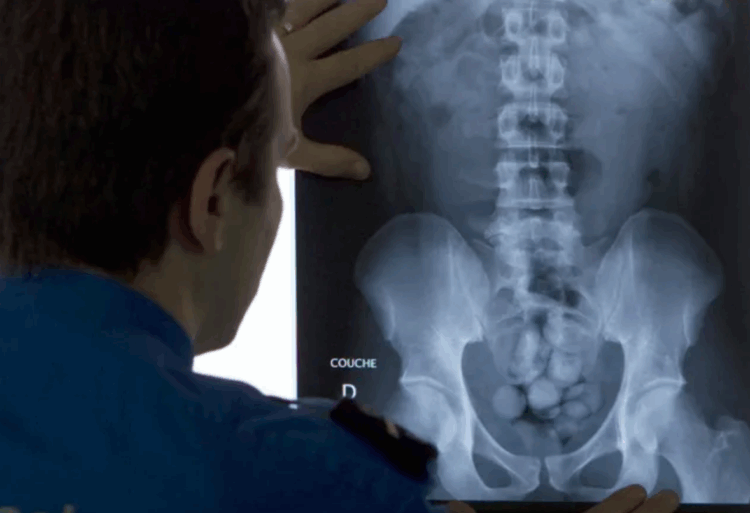

As autoridades alfandegárias desconfiaram da pequena quantidade de bagagem que os dois carregavam e solicitaram radiografias voluntárias, que revelaram objetos anormais no abdômen. Exames de tomografia computadorizada confirmaram a presença de dezenas de cápsulas em formato de casulo.